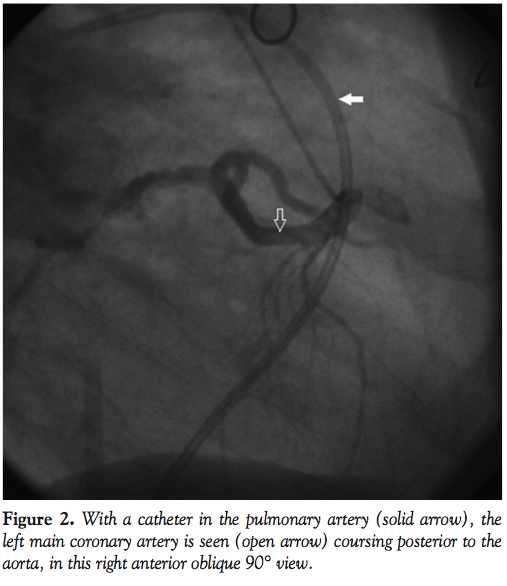

coming off of the LM at a very acute angle, which was felt to be a risk for future stenosis of the LAD. The LM was deemed not to be inter-arterial (running between the aorta and pulmonary artery). During the current admission, cardiac catheterization revealed that both vein grafts were totally occluded. RCA was totally occluded, with filling of the RPDA via collaterals from the left. Additionally, there was a critical 99% stenosis in the proximal LCX (Figure 1). The patient was referred for re-operation CABG. However, the surgeons only considered him a candidate for re-operation if the LM was coursing inter-arterially. Upon repeat cardiac catheterization and by placing a catheter in the pulmonary artery, it was confirmed that the LM actually coursed posterior to the aorta, and not inter-arterially (Figure 2). The LM had an intra-septal course and it gave off large septal branches before bifurcating; however, there was no systolic compression of the LM.

When the LM originates from the right sinus of Valsalva, it may be classified into one of four types: a) the LM passes between the aorta and pulmonary trunk, posteriorly and adjacent to the pulmonary trunk; b) the LM passes anteriorly over the right ventricular outflow tract; c) the LM courses along the crista supraventricularis intramyocardially or subendocardially, surfacing in the proximal interventricular sulcus; and d) the LM may rise to the right of the RCA and pass posteriorly to the aortic root or anterior to the pulmonary trunk.1 In our patient, the LM coursed posterior to the aorta (Figure 2).